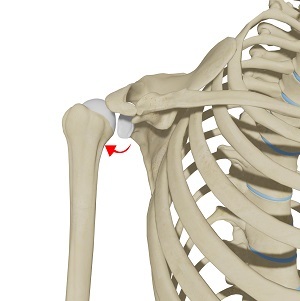

Posterior shoulder instability, also known as posterior glenohumeral instability, is a condition in which the head of the humerus (upper arm bone) dislocates or subluxes posteriorly from the glenoid (socket portion of the shoulder) as a result of significant trauma. A partial dislocation is referred to as a subluxation whereas a complete separation is referred to as a dislocation.

Posterior shoulder instability occurs when considerable force is applied through the arm when the arm is extended in front of the body, rupturing the shoulder capsule, ligaments, and labrum.

The shoulder joint (glenohumeral joint) is a ball and socket joint. A ball at the top of the upper arm bone (the humerus) fits neatly into a socket, called the glenoid, which is part of the shoulder blade (scapula). The labrum is a ring of fibrous cartilage surrounding the glenoid, which helps in stabilizing the shoulder joint. Tendons and ligaments around the shoulder joint provide additional strength and stability to the joint.